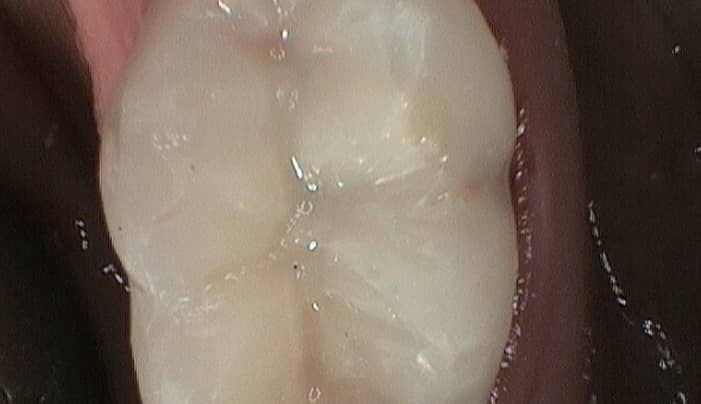

Traditional fillings are made of a metal amalgam made up of copper, tin and silver and are usually silvery looking. More recently, patients have chosen to use a composite material for their fillings which looks much more like a natural tooth.

Most fillings are highly durable and, with good dental care, will last for a long time. Composite fillings can last up to 10 years, while metal amalgam fillings can last for 40 years.